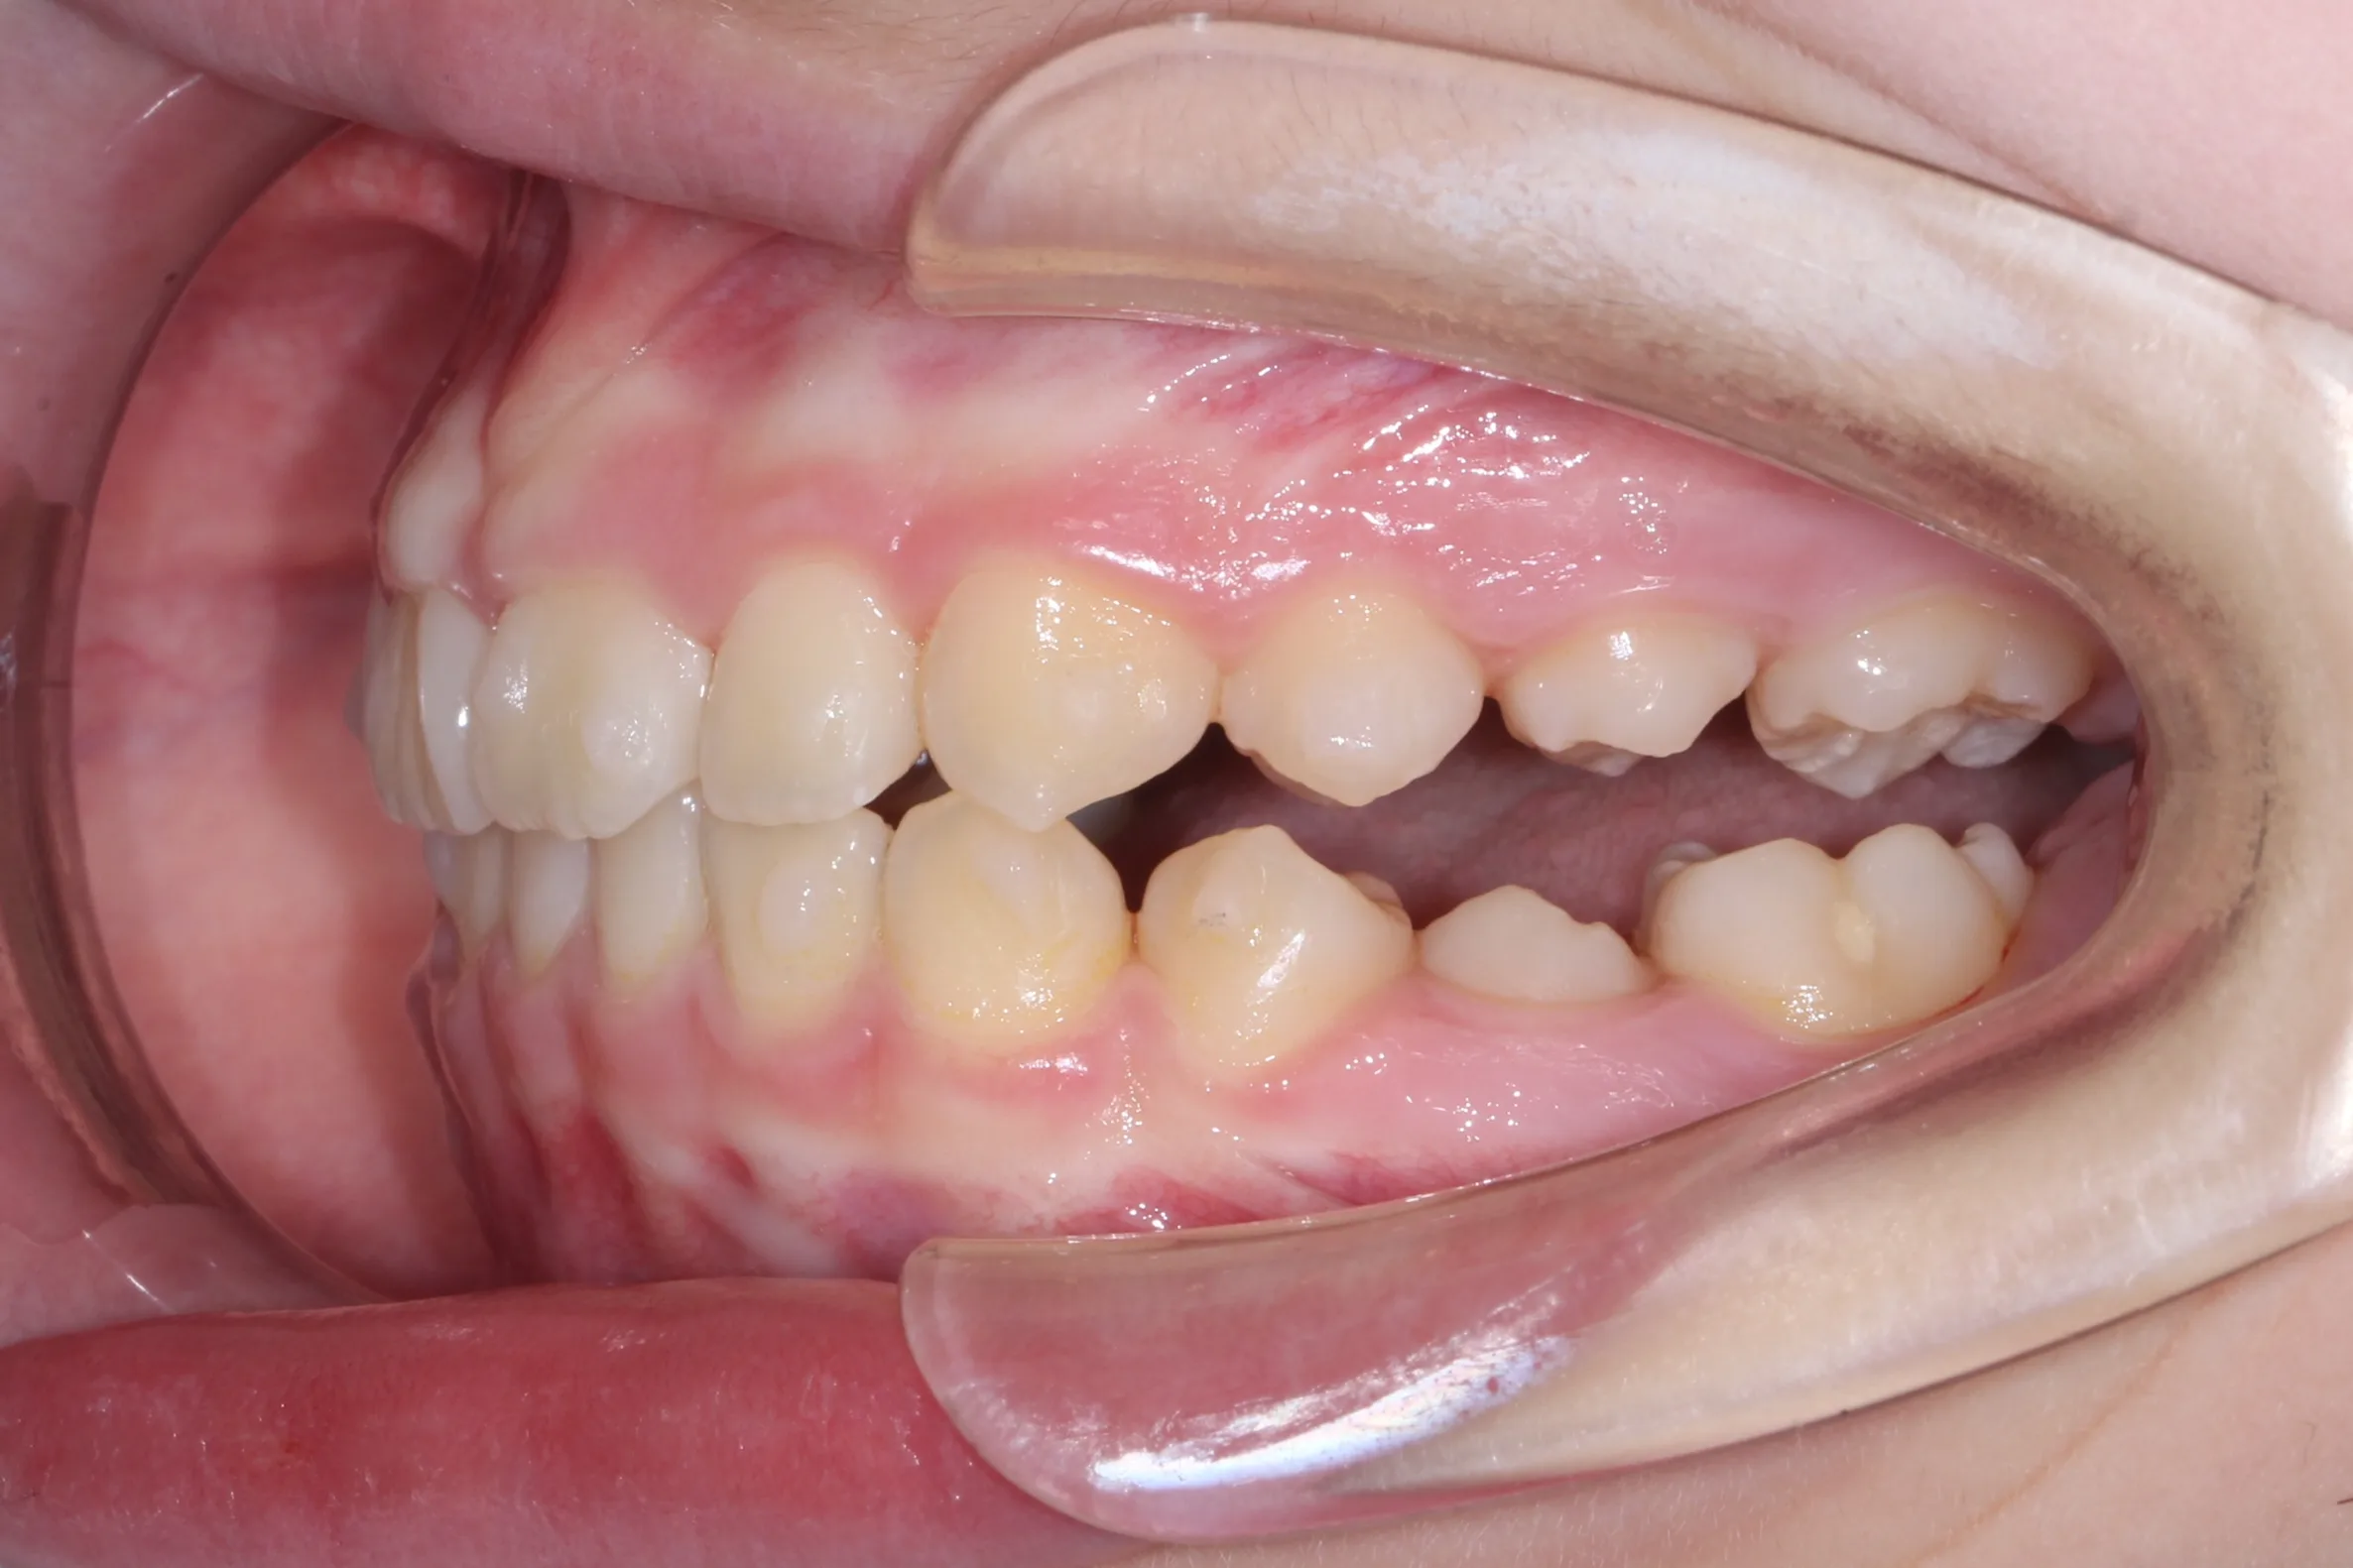

만 11세 환자분께서 튀어나온 앞니와 다물어지지 않는 입술 때문에 내원하셨습니다. 검진 결과 상악 전돌을 동반한 2급 부정교합(Class II malocclusion) 상태였으며, 아래턱의 성장이 다소 부족하여 골격적인 조화가 필요한 상황이었습니다.

이번 치료에는 인비절라인 퍼스트(Invisalign First)에 하악 전방 견인(Mandibular Advancement, MA wing)을 추가하여 치료를 진행하였습니다. 성장기라는 시기적 특성을 적극 활용하여 아래턱의 점진적인 성장을 유도하고, 과도한 상악 전치부 돌출을 개선하는 데 치료의 핵심 전략을 두었습니다.